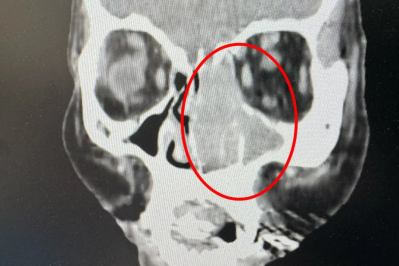

眼睛流泪,元凶在鼻子,长期鼻塞竟然是恶性肿瘤,仁品专家:「早期诊断、规范治疗还有救!」